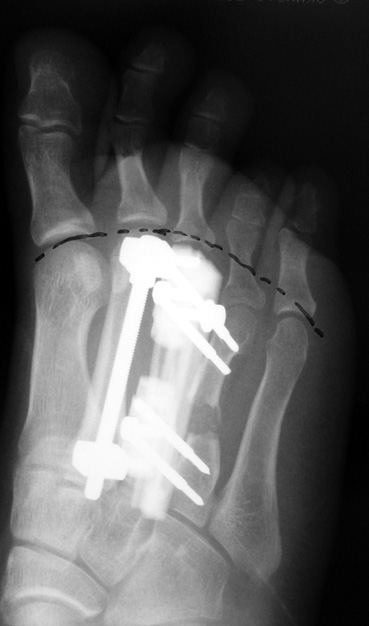

Doğuştan metakarp ve metatars kısalıklarının redavisi için pek çok teknik tanımlanmakla birlikte en çok akut uzatma sonrası kemik uçlarına greft konması ve distraksiyon osteogenezi (kallotasis) kullanılmaktadır. 1 cm.den daha fazla uzatma gereken olgularda kallotasis yöntemi önerilmektedir. Kliniğimizde de metatars ve metakarp uzatma için unilateral eksternal fiksatör ve sirküler eksternal fiksatör yardımıyla distraksiyon osteogenezi yöntemi tercih edilmektedir.